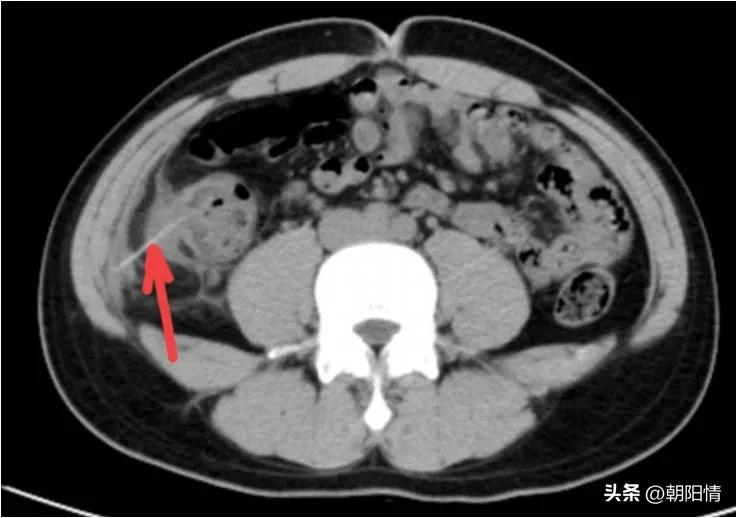

Case10:男性,17岁,腹痛半天就诊,临床可疑急性阑尾炎。行全腹部CT检查:

影像所见:线状异物穿破盲升结肠肠壁及腹膜,累及右侧腹壁肌肉,局限性腹膜炎。

腹腔镜手术证实异物为牙签,肠周、右侧结肠旁沟积脓。